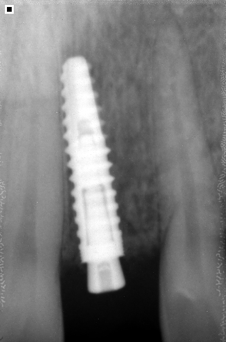

Reemplazamos la pieza dental original por una fabricada en Titanio biocompatible que se introduce en el hueso de la mandíbula, sobre ésta nueva raíz se fija una pieza de metal y cerámica (corona) resistente que se iguala en color y forma con el fin de brindar un aspecto lo más natural posible.

- El implante se fusiona con el hueso mandibular, proporcionando un soporte estable para los dientes artificiales

- Implante fabricado en Titanio Grado V de la más alta pureza.

- Reemplaza la raíz del diente y evita la perdida de hueso.